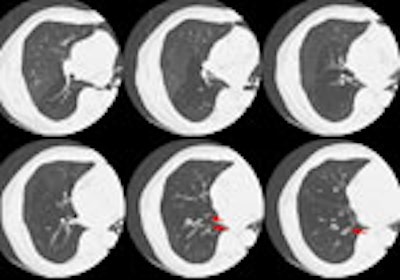

The CT scan demonstrated a water density mass in the right paratracheal region that extended inferiorly into the middle mediastinum to the region of the superior pericardial recess. The cyst was removed surgically and found to be a mesothelial cyst, most likely pericardial, but in an atypical location.